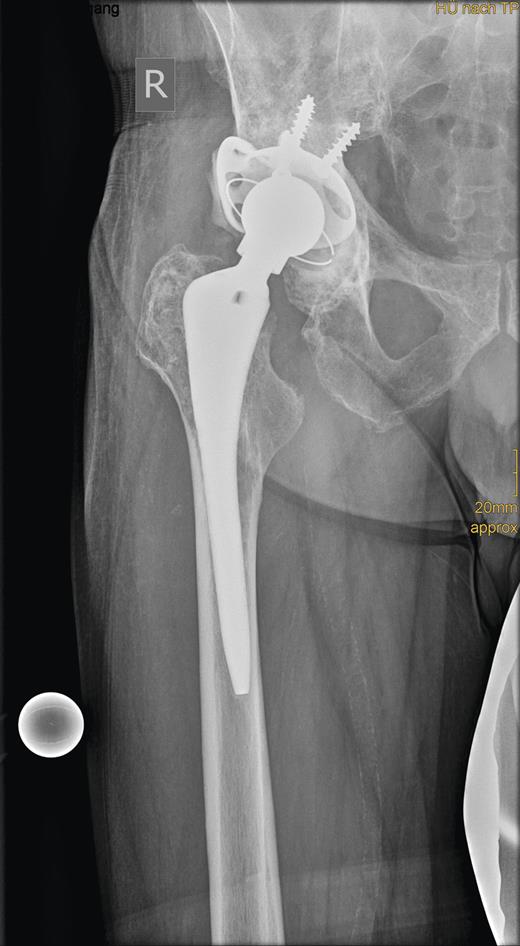

In revision surgery, the stem was fixed but the socket was easily removed and the center of the acetabulum exhibited massive destruction. There was no clear demarcation between the tumor mass, consisting of soft tissue, and its surroundings. After wide resection of the tumor, the bone defect was filled with homologous bone and a 52-mm roof reinforcement ring (Mathys), with a cemented 50-mm low-profile cup (Mathys), was implanted (Fig. 3).

Radiograph showing the roof reinforcement ring with the cemented low profile cup after revision surgery.